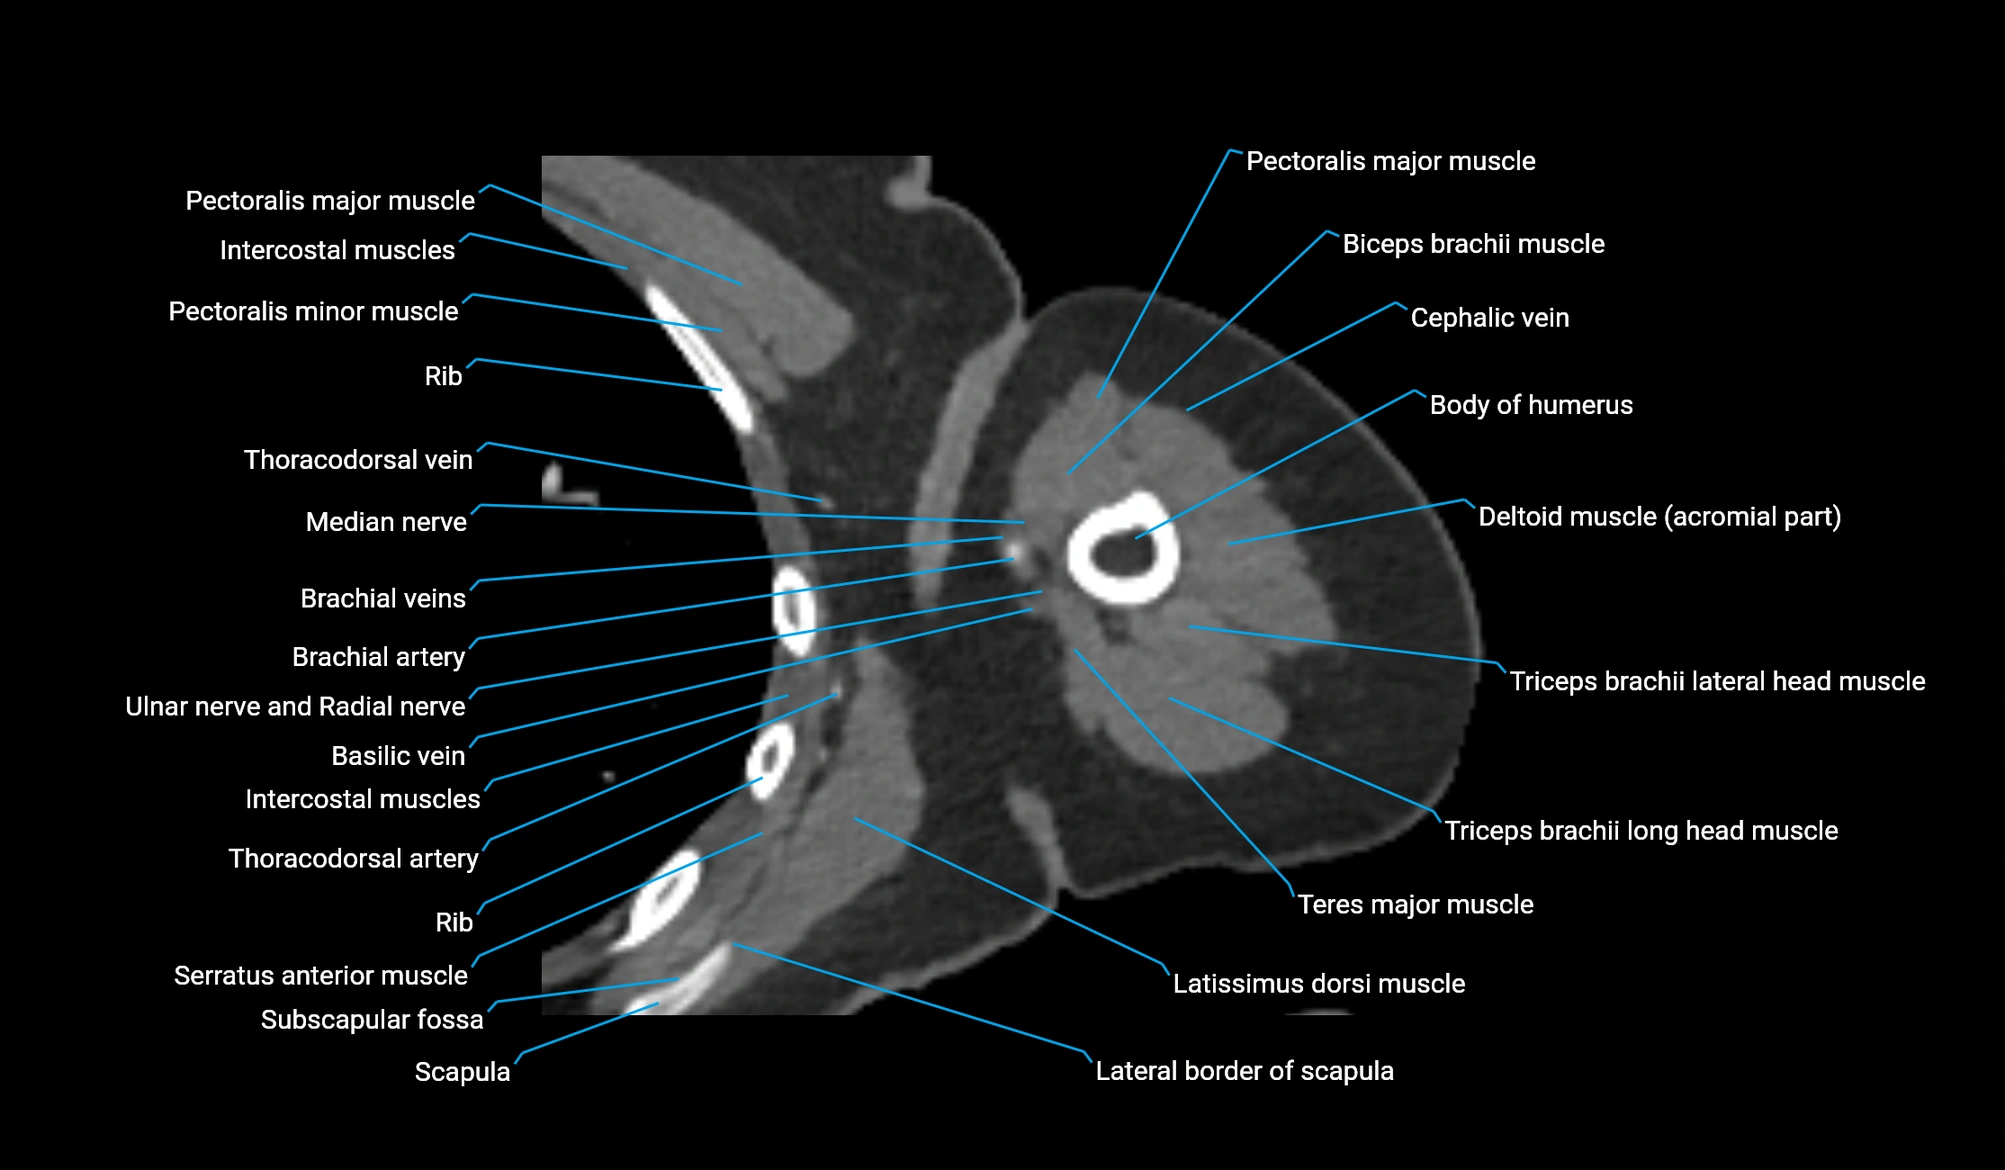

- Basilic vein

- Brachial artery

- Cephalic vein

- Lateral border of scapula

- Long head of triceps brachii muscle

- Lateral head of triceps brachii muscle

- Median nerve

- Pectoralis major muscle

- Pectoralis minor muscle

- Scapula

- Subscapular fossa

- Subscapularis muscle

- Teres major muscle

- Thoracodorsal artery

- Ulnar nerve